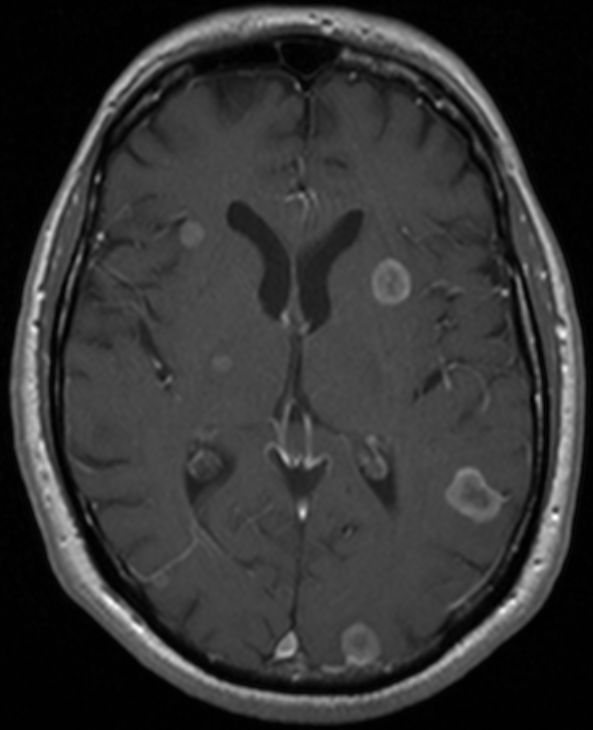

MRT: multiple Hirnmetastasen

70-jähriger Mann, der vor einem Jahr ein Adenokarzinom des rechten Lungenmittellappens hatte. MRT-Untersuchung des Hirns, T1-Sequenz mit Kontrastmittel. Klinisch keine Symptome!